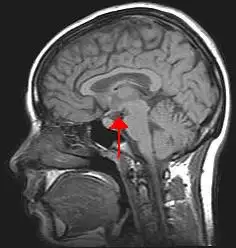

1917年4月,维也纳精神病学学会的会议室里,一位贵族出身的神经科医生正站在讲台上,描述着他从未见过的一组诡异病例。康斯坦丁·冯·埃科诺莫男爵(Baron Constantin von Economo)面前坐着一群困惑的同行——他刚刚告诉他们,一种全新的疾病正在欧洲蔓延,而这种疾病的主要症状是"无法抗拒的睡眠欲望"。 ...

1917年4月,维也纳精神病学学会的会议室里,一位贵族出身的神经科医生正站在讲台上,描述着他从未见过的一组诡异病例。康斯坦丁·冯·埃科诺莫男爵(Baron Constantin von Economo)面前坐着一群困惑的同行——他刚刚告诉他们,一种全新的疾病正在欧洲蔓延,而这种疾病的主要症状是"无法抗拒的睡眠欲望"。 ...